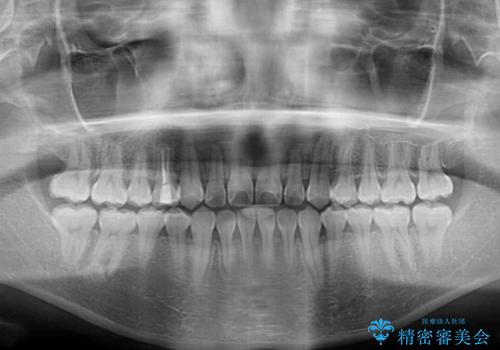

ワイヤー矯正での開咬改善には時間がかかります。

舌の突出癖改善のトレーニングをしっかりと行っていただき、上下前歯が接触する咬み合わせを達成することができました。